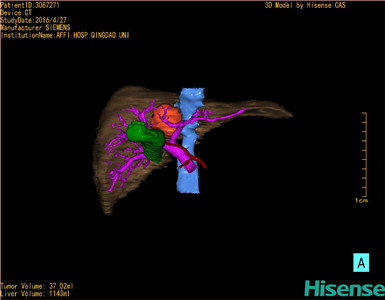

将0.625mm双源薄层CT资料的静脉期和动脉期Dicom格式文件导入海信CAS系统。

通过调节窗宽窗位调整CT序号,对肿瘤,肝实质,胆囊,下腔静脉,肿瘤,肝动脉、门静脉及肝静脉等进行三维重建;系统自动计算肿瘤体积和肝脏体积。

模拟手术操作,自动计算切除肿瘤体积。肝脏体积为1143ml,肿瘤体积为37.02ml,肿瘤体积为肝脏体积的3.2%,通过比对70-80岁正常肝脏体积为1118.08±190.14 ml,通过术前模拟手术,精准判断切除后剩余肝脏体积能耐受,避免肝衰竭发生。

术前手术方案的规划。

术前三维重建:

重建图片